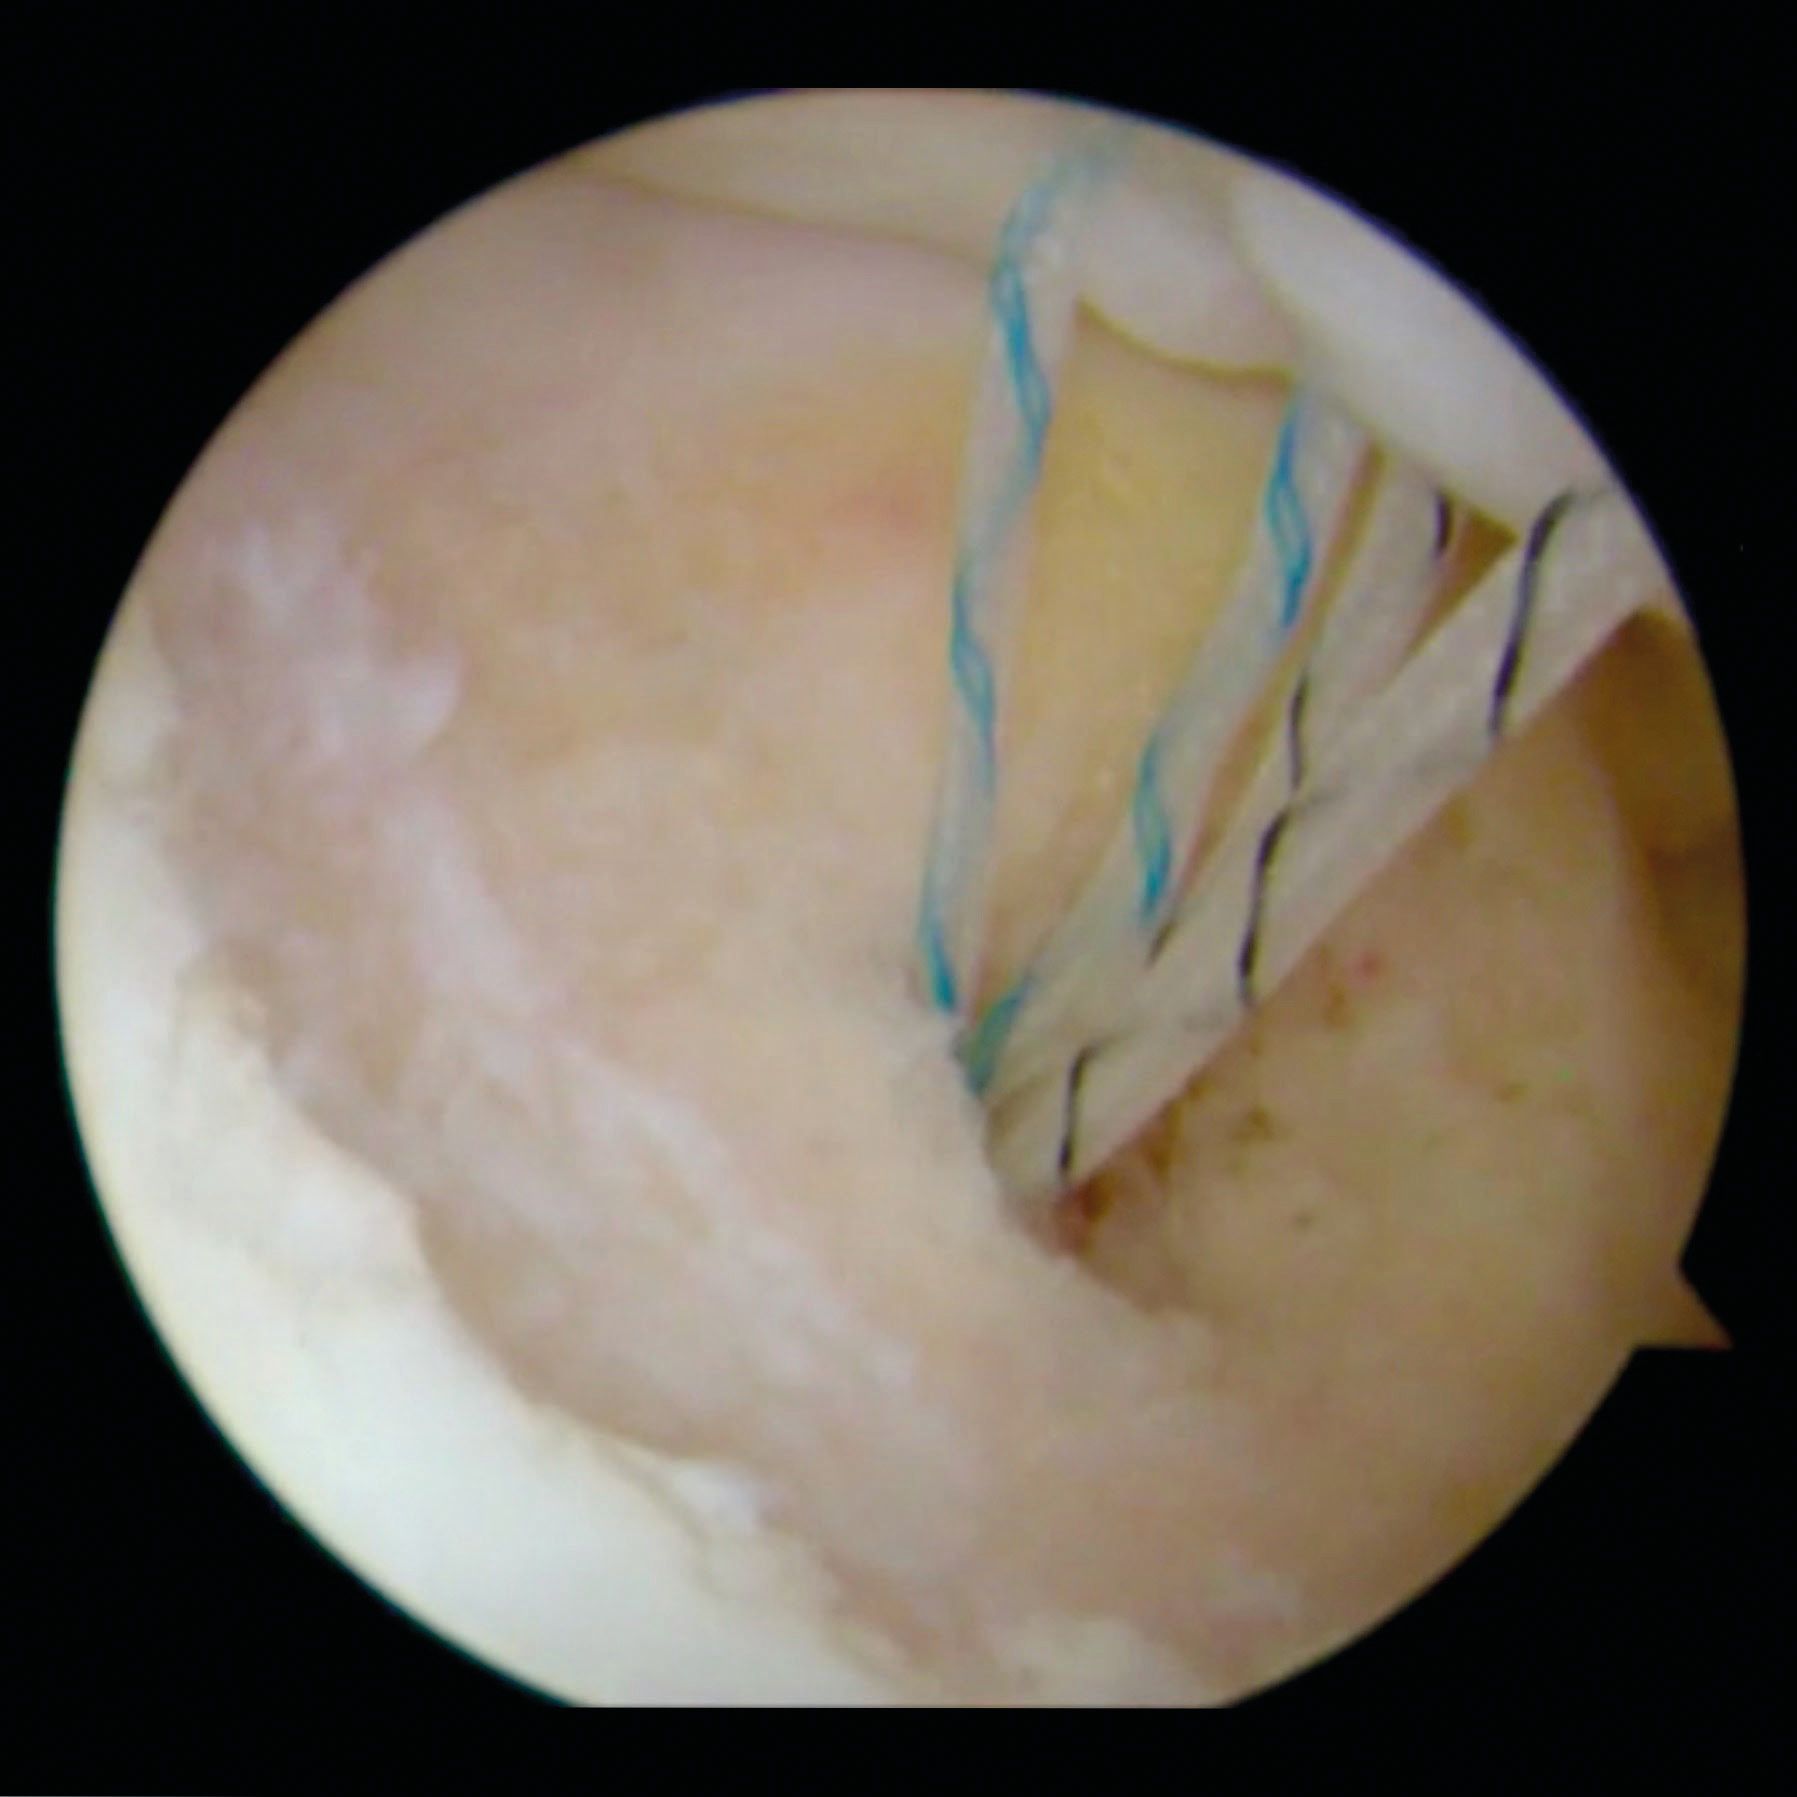

Once the Hill-Sachs anchors are placed and sutures passed through the infraspinatus tendon, the anterior-inferior capsulolabral repair is performed. Only after finishing the anterior procedure, the posterior humeral sutures are tied, percutaneously, through the deltoid and over the infraspinatus tendon. The mattress sutures draw the infraspinatus and the posterior capsule to the abraded bony surfaces, thus achieving a filling (remplissage) of the Hill-Sachs lesion. Figure 5.

The original technique described suture anchors placed into the valley of the defect, with the suture limbs passed directly posterior. Other authors have proposed a modification with a double-pulley technique [25]. One or two anchors can be used depending on the size of the defect. The anchor(s) can be placed in the middle of the valley or into the rim of subchondral bone adjacent to the articular margin [25]. Presently, there is no standardized technique. In vitro, there is no substantial differences between suture anchors placed into the valley of the Hill-Sachs defect vs those placed into the subchondral rim of the humeral head, but a medial suture placement, by its effect on the capsule and the tendon, can result in joint stiffness

and restriction in motion [26]. Figure 6.

Some surgeons prefer to place the arthroscope in the subacromial space when they tie the sutures over the infraspinatus [25] in order to better control the procedure and a suture bridge can be performed between the two anchors.